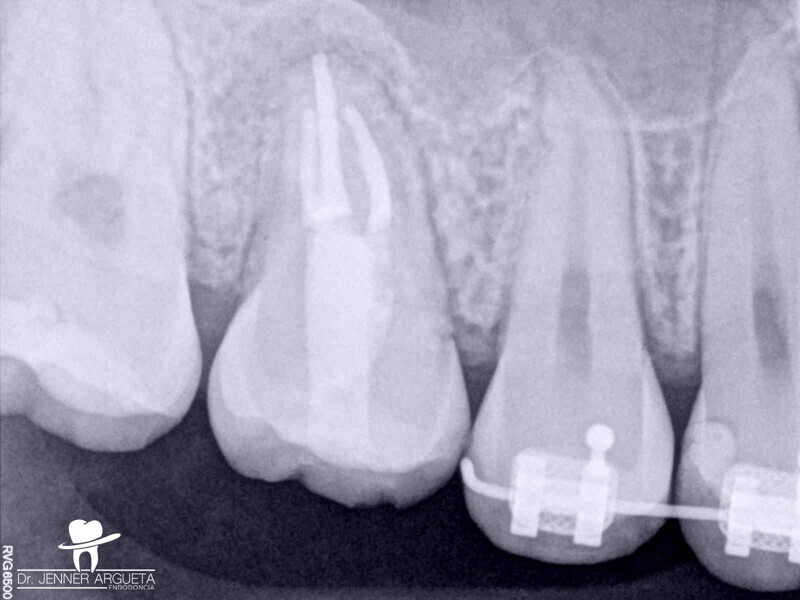

Autogenous transplantation followed by conservative root canal therapy: Three years follow-up